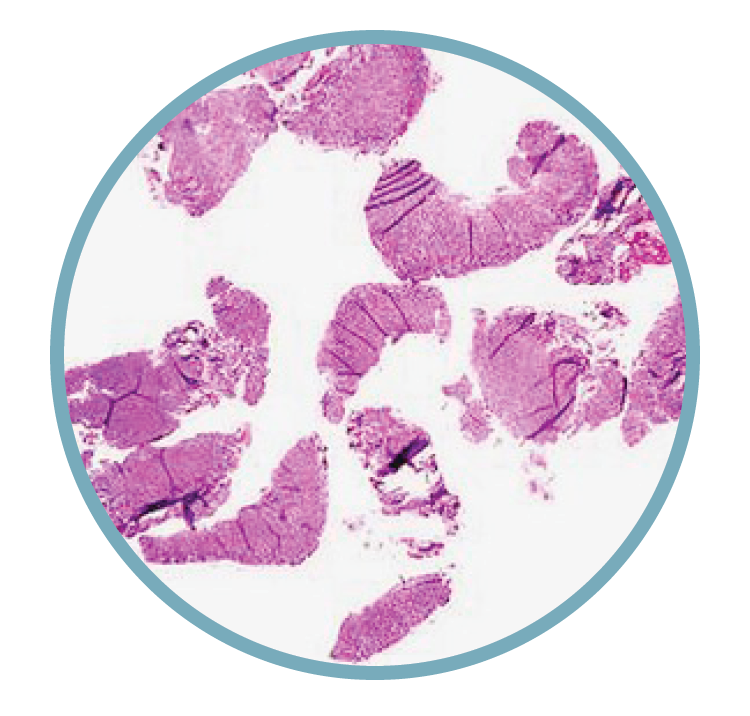

Microscopic view of biological tissue stained pink and purple, showing irregularly shaped cells and structures.

Tissue Fragmentation

Reduces diagnostic clarity, lowers reproducibility, and complicates interpretation.